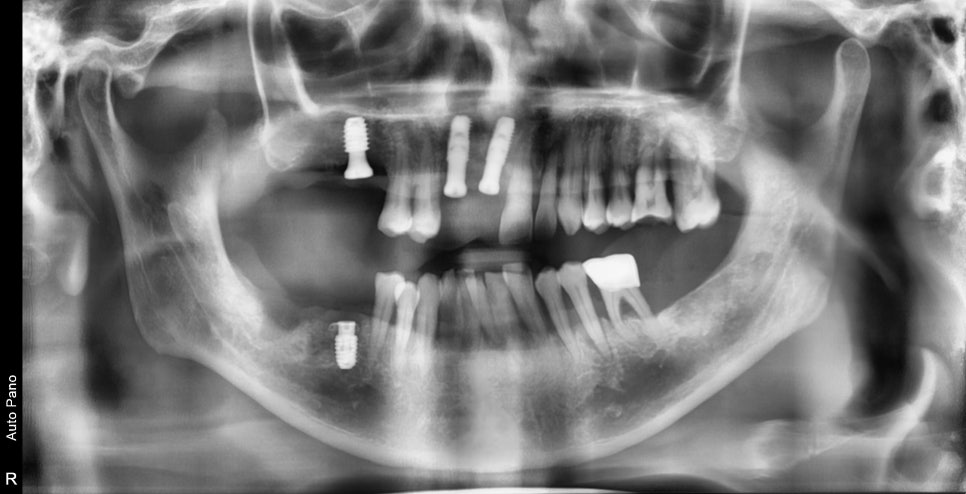

초진 사진입니다.

빨간색 원으로 표시된 부분이 특히 뼈가 많이 녹아 많이 흔들렸으며

나머지 치아들도 전반적으로 동요도가 있었습니다.

구강 내 사진을 보게 됐을 때

정상 잇몸 레벨에서 치은염의 진행으로 잇몸이 많이 내려앉은 상태에서

더욱 깊게 양치가 어렵다 보니 치주염으로 이미 진행이 된 상태였습니다.

다수 치아의 발치가 필요하지만 치료 진행과 더불어 중요한 것은 잇몸 관리였습니다.